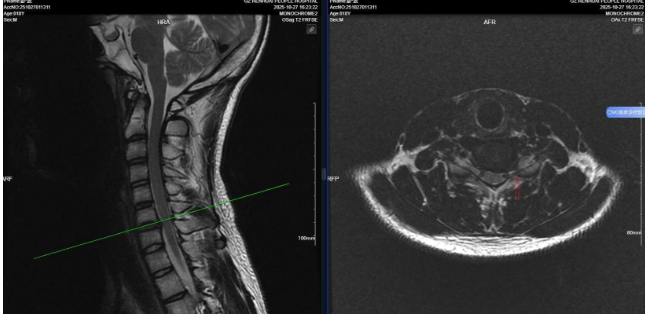

患者彭同学为18岁高三学生,因左侧肩颈部疼痛伴左上肢放射痛、麻木6个月前来就诊,被诊断为颈椎间盘突出症。他是目前我院接诊的年纪最小的颈椎病患者。由于长期受左上肢疼痛困扰,其学习与生活受到严重影响。在尝试保守治疗效果不佳后,考虑推迟手术可能影响学业及患者的康复,经与家属积极沟通后,在上级专家的指导下,决定选择微创手术方案。

为尽快缓解症状、帮助患者早日康复,骨科中心团队经过周密的术前讨论,为其制定了“经椎间孔镜下颈椎间盘摘除术”的微创治疗方案。在骨科中心与手术室团队的协作下,手术顺利完成,在保护神经根和硬膜囊的前提下,成功摘除脱出的椎间盘髓核。该术式避免了传统手术的大切口和广泛肌肉剥离,手术创伤小,患者颈部仅留下0.8厘米的切口。术后患者症状消失,可下床活动,恢复情况良好。